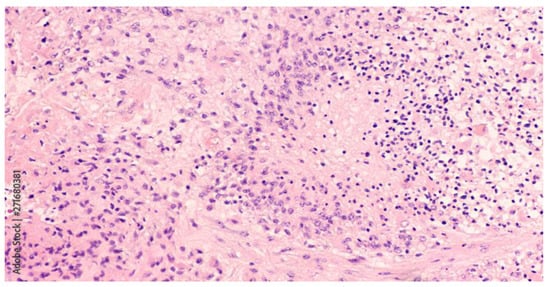

3.1.1. Simulated Microgravity Effects on Glioblastoma Multiforme

3.2.1. Parvovirus and Glioblastoma Multiforme